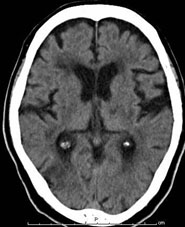

代表例の提示

転移性脳腫瘍 肺癌の脳内転移

[ラジオサージャリー前]

CT(左画像): 左下の黒くなっているところが癌、 造影MR(右画像):左下の周りが白い線で囲まれたようになっているところが癌

[ラジオサージャリー後2ヵ月半]

CT、MRともに癌が縮小している。